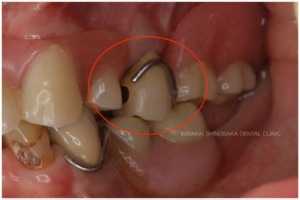

診査・診断の結果、保険内で作製した義歯のプラスチック部分が薄くなっていることと、左上の天然歯1本だけに金具を引っ掛けて支えていたという、非常に不安定な状態のまま義歯を使用されていたため、割れてしまうなどの不具合が頻繁に発生していたことが分かりました。

総義歯を作製するにあたり、複数の残根歯、特に左上に不都合な高さの歯が残っていることが懸念点でした。

(残根歯とは、虫歯や外傷などによって歯の頭の部分が失われ、歯の根だけが歯茎に残っている状態の歯のことをいいます。)

「できれば歯を抜かずに残したい」という患者さまのご意向にお応えし、抜歯は行わず、義歯に影響しないくらいの高さまで調整するだけにとどめた後、上顎用総義歯を作製いたしました。幸い、他の歯や歯周組織に影響を及ぼすほどの虫歯にはなっていなかったため、残根歯は全て抜かずにそのまま残すことができました。